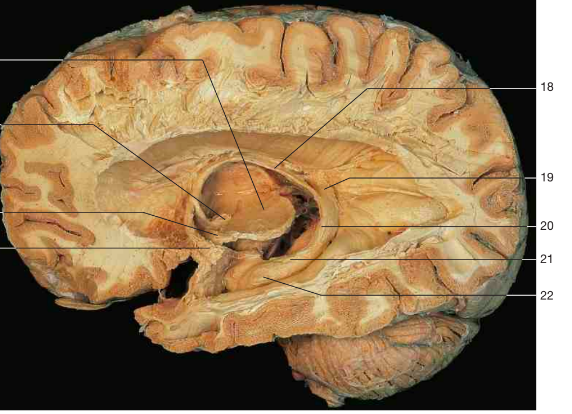

Label 18-22

18 Fornix

19 Longitudinal stria

20 Dentate gyrus

21 Hippocampal fimbria

22 Pes hippocampi